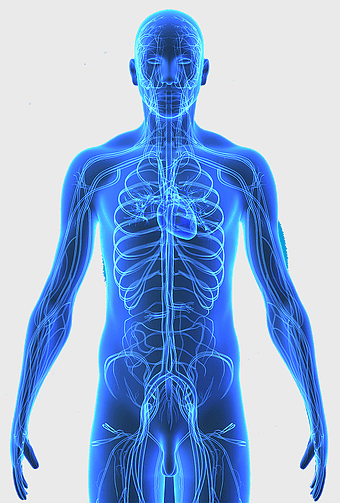

circulatory system diagram, blood vessel network, monochrome line art, pulmonary circulation illustration, vascular tree structure, anatomical line drawing, systemic venous system chart -

blue human anatomy illustration, human circulatory system diagram, digital human skeleton image, electric blue medical figure, human nervous system visualization, human body organ map, human health care graphic -